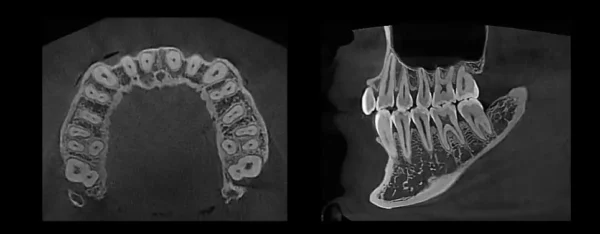

Superior Image Quality

Striking contrast and sharpness of images produced by HDX WILL’s image reconstruction technology